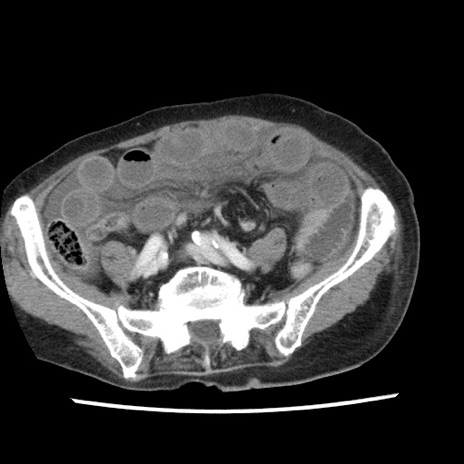

症例1(横断像)

【症例】80歳代女性

【主訴】腹痛

【現病歴】8時間前から腹痛あり来院。

【既往歴】糖尿病、脂質異常症、子宮体癌にて子宮全摘術

【身体所見】意識清明・会話良好だが腹痛で苦悶様、全腹部にわたって反跳痛と圧痛あり

【データ】WBC 13600、CRP 0.14、LDH 224、CK 90